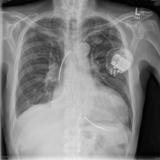

ICD PA

Date: 04/25/2009

Views: 3074